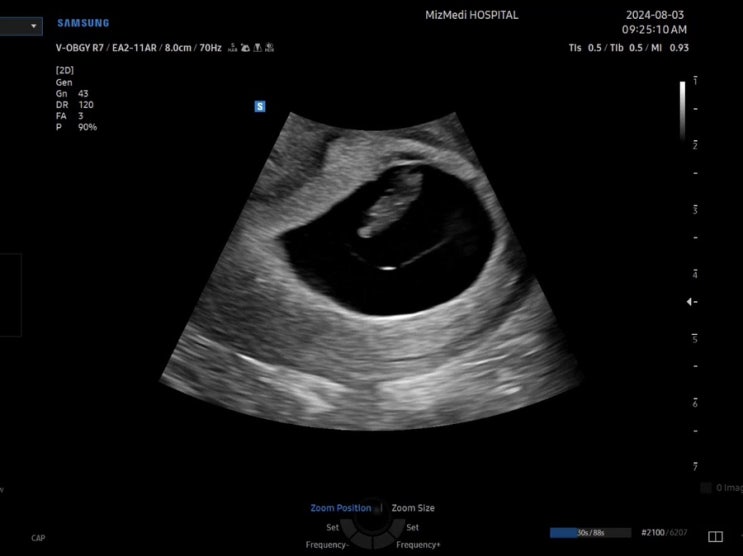

임신 이야기 1 - 임신 3주부터 임신 7주차 이야기

지난 두달은 내 인생에 처음 경험해보는걸로 가득한 시간이었다. 임신부터 유산, 그리고 소파술까지. 행복...